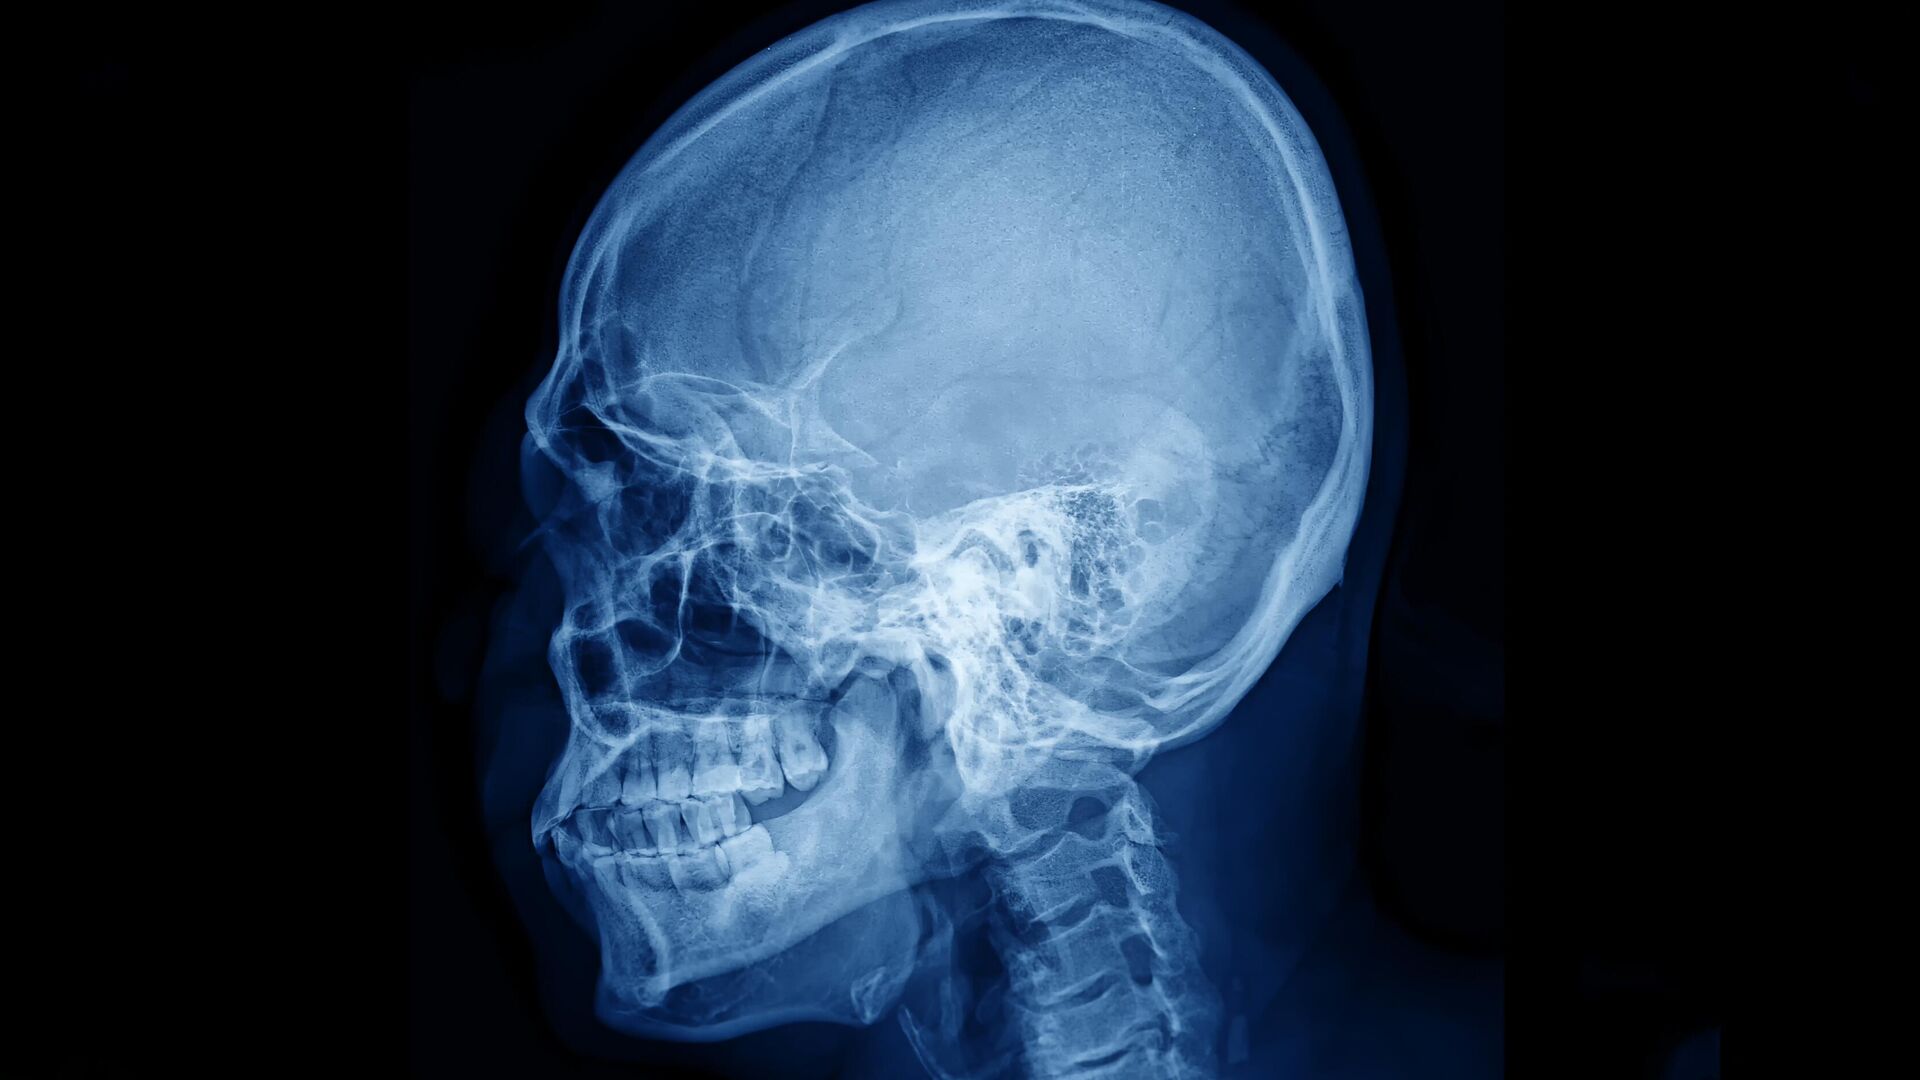

Современные методы визуализации сосудов головного мозга сталкиваются с серьезными техническими ограничениями, связанными с особенностями костной ткани черепа. Для получения четких изображений сосудистой сети часто требуется либо значительное истончение костей, либо создание отверстий в черепной коробке, что является инвазивной процедурой и связано с определенными рисками для пациента. Основная сложность заключается в том, что костный материал сильно рассеивает лазерный свет, используемый в ряде передовых диагностических методик, что приводит к размытию и искажению получаемых изображений.

Одним из таких методов является лазерная спекл-контрастная визуализация, которая широко применяется для наблюдения за кровотоком в головном мозге. Как пояснил младший научный сотрудник лаборатории биомедицинской фотоакустики СГУ Юрий Сурков, лазерный свет, проходя через костные структуры, испытывает сильное рассеяние, что существенно снижает качество карт сосудов и перфузии мозга. Это ограничивает точность диагностики и усложняет оценку состояния мозгового кровообращения.

Современные методы визуализации мозгового кровотока играют ключевую роль в диагностике и исследовании сосудистых заболеваний, однако качество получаемых изображений часто ограничено из-за низкой контрастности сосудов на фоне костной ткани черепа. В ответ на эту проблему группа ученых из Самарского государственного университета (СГУ) совместно с коллегами из Сеченовского университета, Национального медицинского исследовательского центра нейрохирургии имени Н. Н. Бурденко, Национального исследовательского университета «МИЭТ» и Университета Астон в Бирмингеме (Великобритания) разработала инновационный метод, позволяющий приблизительно в два раза повысить контрастность сосудистых изображений, получаемых при наблюдении мозгового кровотока через целый череп.

Ранее при визуализации сосудов через череп многие мелкие сосуды и тонкие ветви сосудистой сети оставались незаметными, поскольку их контрастность была недостаточной на фоне плотной костной ткани. Благодаря новому подходу, сосуды становятся значительно более четкими и различимыми, что позволяет выявлять ранее скрытые участки сосудистой сети и получать более детальную картину кровотока. Это сравнимо с ситуацией, когда вы смотрите на пейзаж через матовое стекло: раньше изображение было размытым и нечетким, а теперь оно становится прозрачным и ярким, позволяя рассмотреть мельчайшие детали.